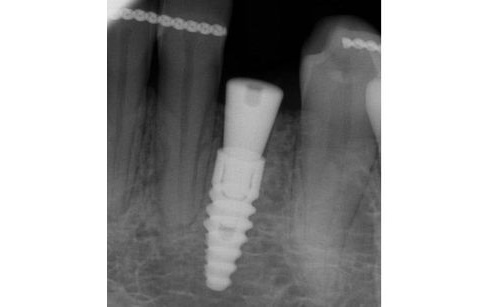

Idealnym rozwiązaniem na uzupełnienie pojedyńczego braku zębowego jest wszczepienie implantu i odbudowa korony zęba.